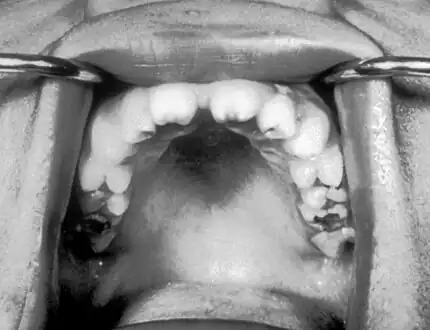

Late onset features include deformity of the nose, lower legs, forehead, collar bone, jaw, and cheek bone.[1] Some of these bone defects can be detected early.[16] There may be a perforated or high arched palate, and recurrent joint disease.[1][4] Other late signs include scarred skin, intellectual disability, hydrocephalus, and juvenile general paresis.[1] Eighth nerve palsy, interstitial keratitis and small notched teeth may appear individually or together; known as Hutchinson triad.[1][18]